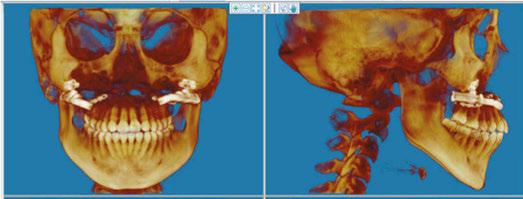

The CBCT image revealed several findings. First, it was apparent that a periapical radiolucency (PARL) existed in association with the overlapping mandibular incisors (Figures 4A – 4C). Figure 4A shows tooth No. 24 with compromised facial alveolar support, while figure 4C shows tooth No. 25 with a greater amount of visible facial bone. In figure 4E, tooth No. 27 is proclined and has compromised facial alveolar support. Lastly, a second PARL was noted surrounding tooth No. 8 (Figure 5).

Treatment plan

The established treatment plan and extraction recommendation for this patient was primarily based on the CBCT image findings with regards to alveolar support and space analysis. It was clear that tooth No. 24 had the least alveolar support and was already experiencing gingival stripping. However, extraction of this tooth alone would not provide enough space to relieve the crowding, as it is already entirely blocked out of the arch. If one were to extract tooth No. 28 also, tooth No. 27 would need to be distalized and retracted into the arch to allow room for the alignment of the remaining incisors. A potentially more efficient plan would be to extract the periodontally compromised tooth No. 27, as its root is already significantly dehisced thru the facial cortical plate making room for proper alignment of tooth No. 26. Therefore, the final treatment plan for this patient is as follows: refer to general dentist or endodontist for evaluation of PARLs on tooth No. 8 and No. 25 (Figures 4A, 5A, and 5B) and extraction of Tooth Nos. 5, 12, 24, and 27 (Figures 6A and 6B).

Figure 3: Panoramic X-ray taken with diagnostic records on December 17, 2020 Figures 5A-5B: 5A. Shows the sagittal view of tooth No. 8 with associated PARL. 5B. Shows the coronal view of tooth No. 8 with associated PARL Figures 6A-6B: 6A. Shows extractions of tooth Nos. 5 and 12. 6B. Shows extractions of tooth Nos. 24 and 27 Figures 4A-4D: 4A. Shows the sagittal view of tooth No. 24 with what appeared to be an associated PARL. Figure 4B shows the PARL from an axial view centered in the mandibular anterior region. Figure 4C shows tooth No. 25 in the sagittal view, closely associated with the PARL. Figure 4D shows the 3D model of the maxillary and mandibular arches. Figure 4E shows tooth No. 27 in the sagittal view A. B. D. C. E. A. A. B. B.